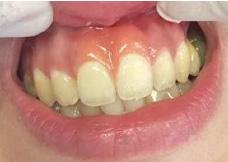

Lâexamen exobuccal Ă©tait sans particularitĂ©s. Lâexamen endobuccal a objectivĂ© une inflammation marginale modĂ©rĂ©e Ă sĂ©vĂšre gĂ©nĂ©ralisĂ©e avec un indice dâOleary Ă 68%, un indice gingival (BoP = Bleeding on Probing) Ă 76%, et un trama occlusal sur 42 (Figure 1). Le bilan parodontal montre des sites avec une profondeur de sondage (PS) de 12mm, et plus de 50% des dents prĂ©sentant une perte dâattache â„ 5mm. Le bilan radiographique a montrĂ© des pertes osseuses terminales, avec un rapport perte osseuse/Ăąge Ă 4,5 (Figure 1)

La thĂ©rapeutique Ă©tiologique a consistĂ© en une Ă©ducation Ă lâhygiĂšne bucco-dentaire, une Ă©limination des facteurs de rĂ©tention de plaque, lâextraction 42+rĂ©section radiculaire et rĂ©alisation dâune contention en fibre de verre avec la couronne ; dâune instrumentation non chirurgicale supra et sous gingivale

par quadrant (3) combinĂ©e Ă une antibiothĂ©rapie (3,4). Une chirurgie avec lambeau dâaccĂšs selon la technique du lambeau avec incision intrasulculaire (open flap) a Ă©tĂ© rĂ©alisĂ©e sur la 46. Une thĂ©rapie parodontale de soutien associĂ©e Ă une phase correctrice a Ă©tĂ© mise en place aprĂšs la thĂ©rapie parodontale active (5). La rĂ©habilitation orale a consistĂ© dans un premier temps Ă rĂ©aliser une correction orthodontique (Figure 2) ; et dans un second temps la conception dâune Ă©pithĂšse gingivale (Figure 3)

AprĂšs 6 mois, pas de profondeurs de poches â„ 6mm, avec un indice de plaque Ă 9% et un indice gingival < 10%. La thĂ©rapeutique non chirurgicale a permis un gain dâattache

stable qui sâest traduit par une diminution des profondeurs de sondage en regard de la 11, 21, et 36 dont le pronostic Ă©tait dĂ©favorable, mais aussi lâapparition dâimportantes rĂ©cessions postthĂ©rapeutique (Figure 4). La chirurgie avec lambeau dâaccĂšs a permis Ă©galement dâamĂ©liorer le niveau osseux de la 46. Le pronostic gĂ©nĂ©ral Ă long terme de la patiente a Ă©tĂ© amĂ©liorĂ©.

La réévaluation Ă 3 mois a montrĂ© une amĂ©lioration de lâĂ©tat parodontal avec plus de 90% de sites prĂ©sentant des PS †4mm (3). LâefficacitĂ© du dĂ©bridement mĂ©canique non chirurgical associĂ© Ă un bon contrĂŽle de plaque individuel dans le traitement des parodontites sĂ©vĂšres a Ă©tĂ© largement documentĂ©e dans plusieurs revues systĂ©matiques (6). Toutefois, la prĂ©sence dâune poche rĂ©siduelle de 6mm avec saignement au sondage sur la 46 reprĂ©sentait un rĂ©sultat incomplet et a nĂ©cessitĂ© dans notre cas un traitement chirurgical par lambeau dâaccĂšs afin dâĂ©viter la progression de la maladie (7).

La rĂ©cession post-thĂ©rapeutique est une observation commune aprĂšs une instrumentation non chirurgicale, particuliĂšrement au niveau des poches profondes et/ou dâun phĂ©notype gingival fin. Notre patiente prĂ©sentait une RT3 sur les incisives centrales rendant son sourire inesthĂ©tique (trou noir). Les restaurations dentaires directes et indirectes et/ou Ă©pithĂšses pouvant ĂȘtre envisagĂ©es (5) ; nous avons optĂ© pour une solution moins invasive en rĂ©alisant une Ă©pithĂšse gingivale. Peu coĂ»teuse et pratique, elle a permis dâoptimiser le rĂ©sultat esthĂ©tique et fonctionnel dans un contexte socio-Ă©conomique limitĂ©.

Figure 4 : (a) Vue clinique Ă 6 mois ; (b) bilan radiographique Ă 3mois (b) ; (c) Retro alvĂ©olaire sur la 46 avant et aprĂšs lambeau dâassainissement